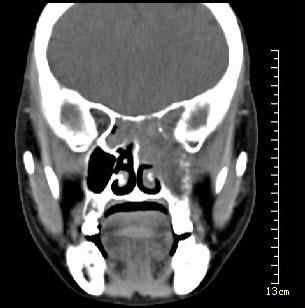

问题 男性50岁,涕中带血半年,体检发现右侧颈部多个硬结,CT扫描如图所示,请选择正确的描述和结论()

选项 A.右侧筛窦内见软组织块影,边缘不规则 B.软组织影累及对侧筛窦、右侧上颌窦 C.右侧眶内壁、上颌窦壁及颅底骨质破坏 D.考虑为右侧筛窦黏液性囊肿 E.考虑为右侧筛窦癌

答案 ABCE